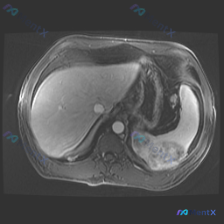

最近看到一个腹部MRI的病例,觉得在鉴别诊断上挺有代表性的,整理一下资料和思路跟大家分享。 先看影像资料(轴位T1序列) - 肝脏、胰腺、胆道、双肾及腹膜后:都没看到明显异常信号或占位,肝内血管、胆总管也不宽,腹膜后没见肿大淋巴结。 - 脾脏(重点):形态大致正常,但实质内有一个边界比较清楚的异常信...